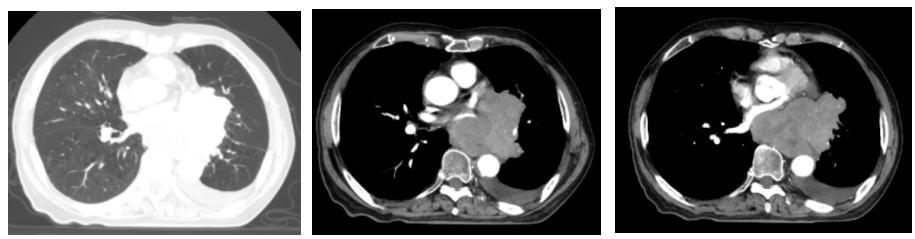

胸部增强CT(2022-05-23):1、左肺门占位(较大截面约7.8cm×8.3cm)伴纵隔多发肿大淋巴结、远端阻塞性肺炎、考虑中央型肺癌,累及左肺动脉及左心房、心室不除外。2、双肺肺气肿。3、左侧胸腔积液,累及左侧胸膜可能。4、心包少量积液。5、肝内多发小囊肿可能。

2022-07-19(2周期后)胸部、全腹部增强CT:1.肺癌复查,较前(2022-05-23)左肺门占位明显减小,左肺下叶远端阻塞性改变较前范围减小;2.双肺肺气肿;3.左侧胸腔积液,累及左侧胸膜可能,较前略增多;4.心包少量积液,较前增多;5.肝内多发囊肿;右肾上极小囊肿;6.肝左叶内小海绵状血管瘤可能;7.前列腺增大伴钙化。

2022-09-30(4周期后)胸部、全腹部增强CT:1.肺癌复查,较前(2022-07-19)左肺门占位减小,左肺下叶远端阻塞性改变较前范围减小;2.双肺肺气肿;3.左侧胸腔积液,累及左侧胸膜可能,较前减少;4.心包少量积液,大致同前;5.肝内多发囊肿;右肾上级小囊肿;6.肝左叶内小海绵状血管瘤可能;7.前列腺增大伴钙化。

2022-11-21(6周期后)胸部、全腹部增强CT:左肺门占位较前(2022-09-30)减小,左肺下叶远端阻塞性改变较前变化不大;左侧胸腔积液,累及左侧胸膜可能,较前减少;心包少量积液,大致同前。

疗效评估:PR(接近CR)。